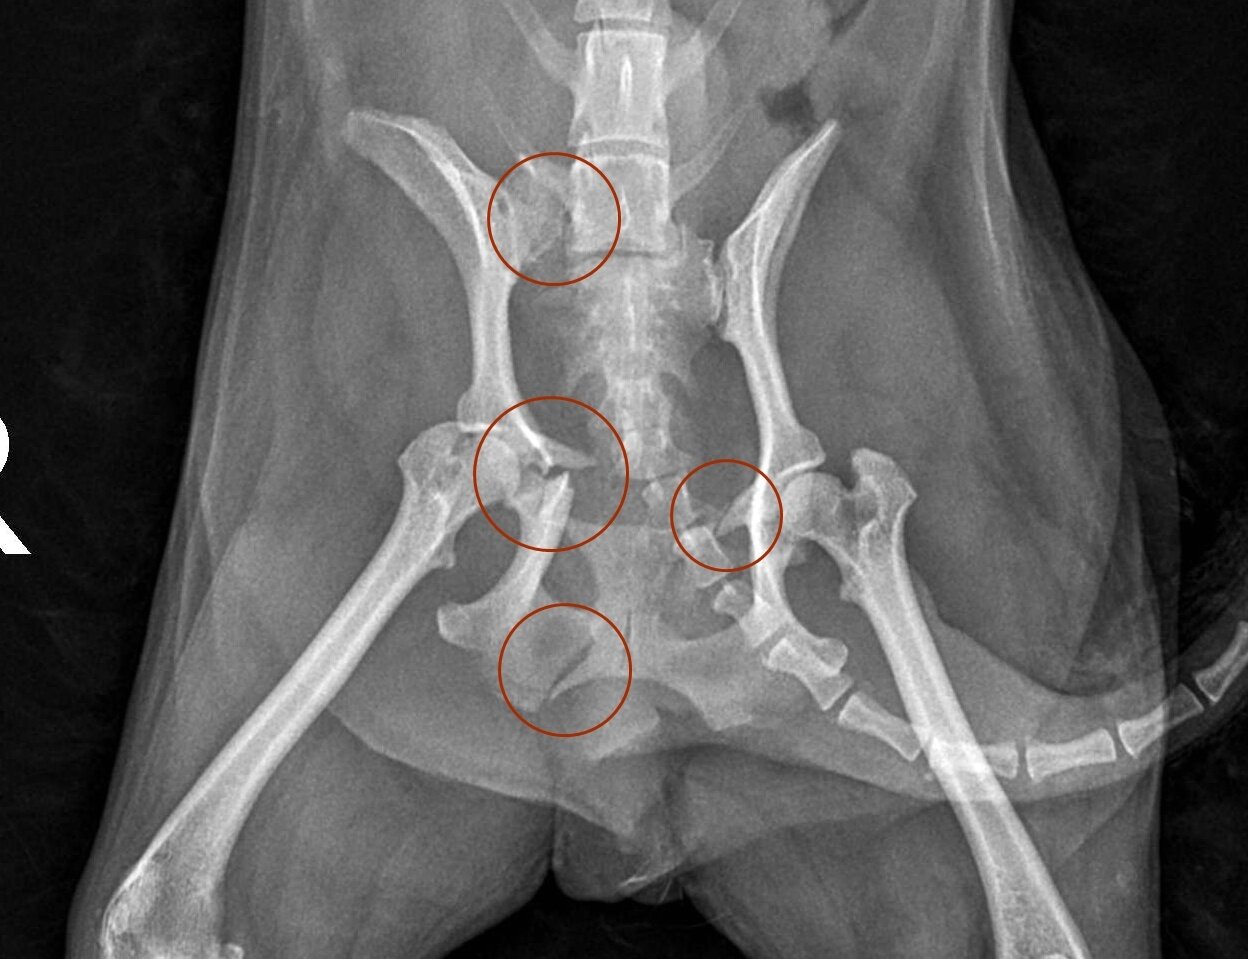

본문 이미지 - 교통사고로 척추 천추가 골절된 반려견의 방사선 사진(예은동물의료센터 제공) ⓒ 뉴스1

교통사고로 척추 천추가 골절된 반려견의 방사선 사진(예은동물의료센터 제공) ⓒ 뉴스1